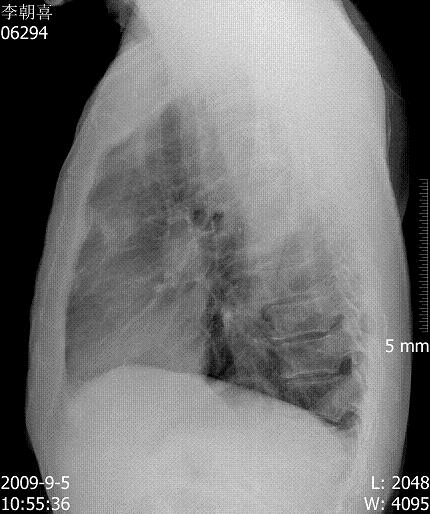

m ,59y,08年12月诊断左侧中央型肺癌,今日复查块影不明显,患者不愿再作ct.

08年cr及ct图像:

今日片: